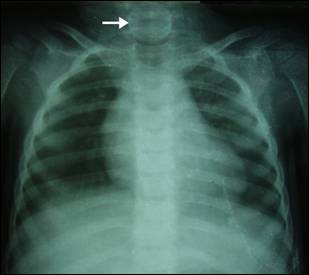

Figure 3:

X-ray neck &Chest: showing faintly visible aluminum coin in the cervical

esophagus (Arrow) in the 2nd patient.